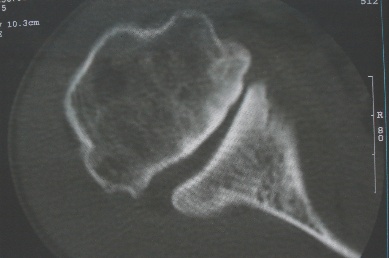

右上肢活动不便多年,最近加重。右肱骨肿瘤,请会诊!

骨软骨瘤恶变可能性大

右肱骨近断骨软骨瘤伴临近关节退变.有无恶变建议进一步检查.

右肱骨近断骨软骨瘤伴临近关节退变。

病变边缘轮廓清晰无骨质破坏,邻近软组织不肿胀,不支持肿瘤恶变。